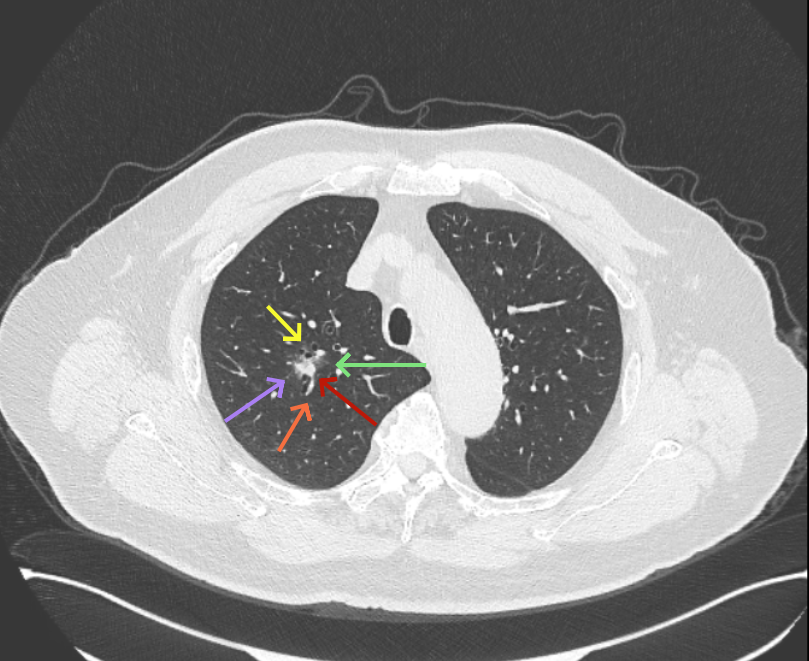

方形的是25年的,红色的主病灶,磨玻璃密度伴少许略偏高点密度,但还说不上典型混合磨玻璃病灶,考虑原位癌或微浸润性腺癌可能性大;蓝色的轮廓与边界欠清,位置靠上叶中央,无法段切或楔切;黄色的多发均淡而纯,分布在两肺。圆形粉色的是主要的两处23年时的样子,对比说不上很明显进展。鉴于若手术得切肺叶,何况两肺他处仍的结节,年纪又74了。我倾向保守点,先6-9个月复查,等进展并风险增加再来考虑怎么办的事。意见供参考!

病灶没有确切纵隔窗可见的实性成分,但与血管关系较为密切。